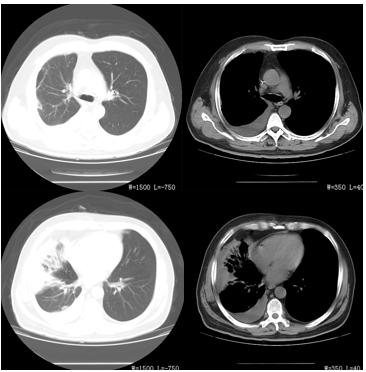

6月21日,患者T 38.7℃,血压多巴胺8~10μg/(kg•min)泵入维持在110~125/65~76mmHg,心率110~118次/分,呼吸25~31次/分,干咳,无痰,稍活动后气短,酱油色尿量约280ml,送检尿中肌红蛋白检查阳性(硫酸铵法),尿常规提示尿沉渣示红细胞计数5个/μl,尿潜血( -),尿蛋白、尿糖、尿酮体均阴性。CRP 201.1mg/L,PCT 3.74ng/ml。6月25日热退,T36.5℃ 。6月27日患者已无发热3日,干咳,气短减轻,血压102~115/63~75mmHg(无需血管活性药物),心率87次/分,呼吸23次/分,文丘里面罩吸氧(氧浓度50%)下血氧饱和度达到96%,血气分析提示PH 7.39,PCO2 40.7mmHg,PO2 102mmHg,氧合指数为204。尿量为2245ml,为淡黄色。尿常规无异常;血常规提示WBC 11.8×109/L,N% 84.8%(较前均有改善);血酶学:ALT 124U/L,AST 97U/L,CK 544U/L,CK-MB 23.6U/L,LDH 600U/L,HBDH 614U/L,MB 176.8U/L,CTNI 0.29μg/L(较前均降低)。血BUN 12.26U/L,Cr 225.9μmol/L,TP 56.6g/L,ALB 28U/L,K+3.11mmol/L,Na+137.6mmol/L,Cl-100.5mmol/L,Ca2+2.08mmol/L;TBIL 5μmol/L,DBIL1.6μmol/L,IBIL 3.4μmol/L;CRP37.83mg/、PCT 1.24ng/ml,上述实验室检查均较前改善。凝血全项PT 14秒,PTA 73.1%,APTT 27秒,DD 1.2mmol/L。6月29日患者精神状态好转,5日无发热,干咳,无明显气短,血压112~134/65~80mmHg(无需血管活性药物),心率84次/分,呼吸19次/分,尿量每日为2000~2800ml之间,肾功(BUN、Cr)、酶学(CK、CK-MB、LDH、AST)均恢复正常,复查胸CT示右肺可见斑片状、索条状高密度影,部分呈实性改变。右侧胸腔积液可见弧形高密度影(图9-2A、9-2B、9-2C、9-2D)。

图9-2A、9-2B、9-2C、9-2D 胸CT 2015-6-29 右肺可见斑片状、索条状高密度影,右侧胸腔积液可见弧形高密度影